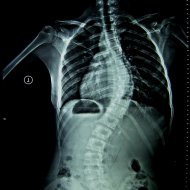

Farklı tipte skolyozu olan hastaların ameliyat öncesi ve sonrası fotoları: